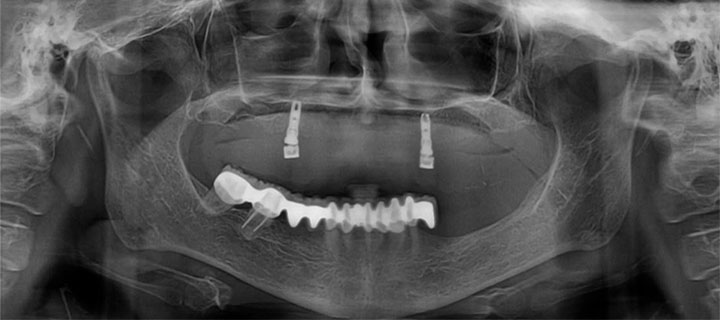

Paciente femenino de 68 años de edad, a la evaluación clínica, se observa edéntulismo total de la arcada superior, entre los hallazgos radiográficos, se encontraron dos implantes dentales a nivel de primeros premolares, así mismo, se observó poco remanente oseo en maxilar, se propuso la colocación de implantes dentales con la técnica all on 6 y un implante pterigoideo para refuerzo.

Rx panorámica postoperatorio inmediato de la colocación del implante pterigoideo

A los meses de espera de la osteointegración de los implantes, se procedió a la rehabilitación total de la cavidad oral, logrando devolverle a la paciente estabilidad, estética y función.